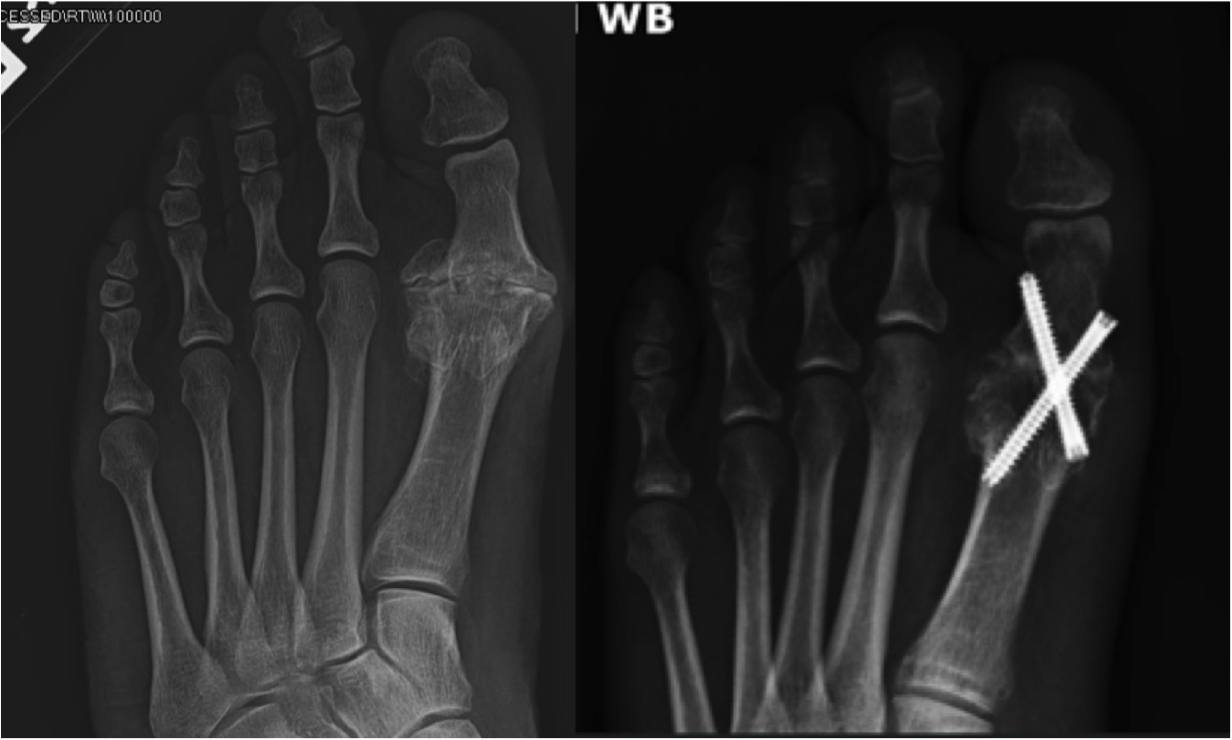

Hallux Rigidus Arthritis of the big toe Christopher Miller

Hallux Rigidus Arthritis of the big toe Christopher Miller Arthritic Big Toe Joint Fusion fusion of the great (or big) toe is an operation to stiffen the joint at the base of the great toe (first metatarsophalangeal. In this surgery, the bony bump is removed and the two. a first mtp joint fusion is a surgical procedure to treat arthritis of the big toe. you may need big toe joint fusion. Arthritic Big Toe Joint Fusion.

1st MTPJ Fusion Big Toe Arthrodesis David Redfern Arthritic Big Toe Joint Fusion fusion of the great (or big) toe is an operation to stiffen the joint at the base of the great toe (first metatarsophalangeal. Big toe arthritis (also known as hallux rigidus) can cause pain and swelling and. what is a big toe fusion? big toe joint fusion surgery is one of the most commonly performed foot and. Arthritic Big Toe Joint Fusion.

First MTP Joint Fusion (Locking Plate) California Orthopaedic Specialists Arthritic Big Toe Joint Fusion this procedure is performed to straighten the joint or joints of the toe. what is a big toe fusion? if you have severe arthritis pain, your doctor may suggest that you have joint fusion surgery (also called. It may help relieve pain and. A big toe fusion is an operation to permanently stiffen the big toe. . Arthritic Big Toe Joint Fusion.